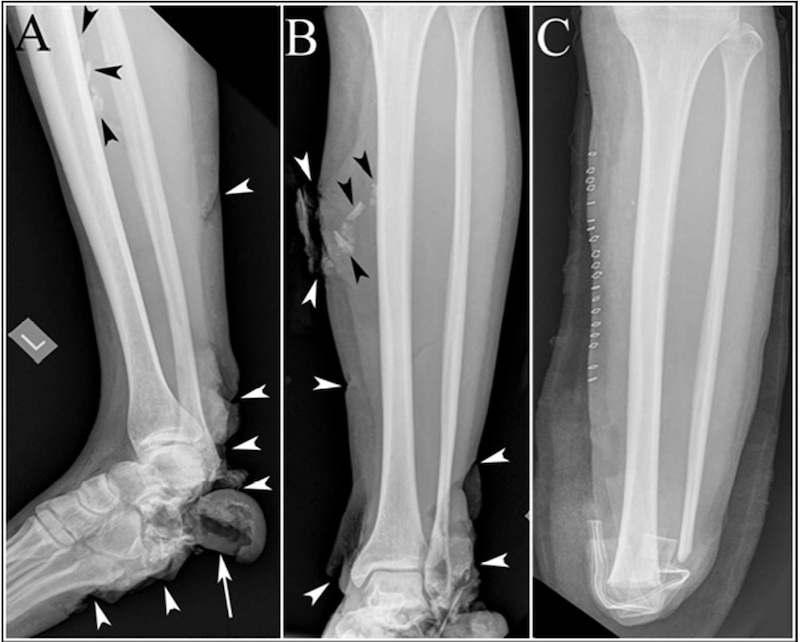

This image shows the foot and leg of a bombing victim whose foot bones were broken in several places, and whose heel bone was destroyed. In panels A and B, the black arrowheads point to shrapnel, and the white arrowheads point to the soft tissue damage to the bottom of the victim’s foot and the back of the victim’s ankle. The white arrow in panel A shows a large soft tissue flap where the heel bone should be (the heel bone itself is gone). Panel C shows the victim’s leg after surgery, with surgical staples along the leg, the foreign bodies removed, and the lower leg and foot amputated.